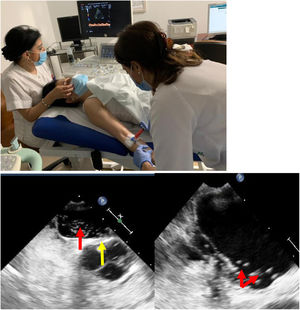

Diagnóstico del foramen oval permeableLa combinación del Doppler transcraneal (DTC), la ecocardiografía transtorácica (ETT) y la ecocardiografía transesofágica (ETE), implementadas con test de burbujas en situación basal y tras maniobra de Valsalva, completarían las pruebas diagnósticas disponibles12 (fig. 1).

Pruebas diagnósticas en FOP.

a) Doppler transcraneal con test de burbujas. b) Ecocardiografía: FOP con aneurisma del tabique interauricular. Izquierda: tabique protruyendo (flecha amarilla) y pase de burbujas a través del FOP (flecha roja). Derecha: aurícula izquierda con numerosas burbujas (flechas).

Imágenes cedidas por la Unidad de Ictus y Laboratorio de Neurosonografía. Servicio de Neurología. Unidad de Ecocardiografía. Servicio de Cardiología. Hospital Reina Sofía de Córdoba.

El DTC es un método seguro y con buenos resultados para detectar la existencia de un shunt derecha-izquierda intracardiaco. Se debe asociar siempre al test de burbujas. Este test, que no precisa de una técnica excesivamente compleja, se realiza canalizando una vía periférica braquial y perfundiendo en bolo un suero fisiológico (suero salino sonicado), o contraste no yodado (habitualmente gelafundina al 4%). Se debe agitar durante su perfusión, para crear microburbujas, y realizar maniobras de Valsalva para favorecer la apertura de la comunicación. Esta situación permite documentar la existencia de FOP mediante efecto Doppler con un transductor interpuesto al nivel de la ventana temporal. Si existe un shunt derecha-izquierda auricular se puede detectar mediante ultrasonidos, por las turbulencias que el flujo provoca coincidiendo con la instilación del suero (fig. 1a).